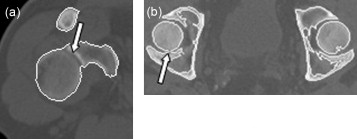

Como ejemplos, observamos que en la figura 7 a la articulación del hombro derecho se detecta de manera incorrecta, identificándose el húmero como parte de la escápula, y la figura 7 b muestra un corte perteneciente a la pelvis; en este caso, el fémur izquierdo se identifica como parte del hueso iliaco, cosa que no sucede con el lado derecho.

Figura 7. Casos donde falla el algoritmo de detección de contornos: a) articulación del hombro derecho, y b) articulación del fémur. |